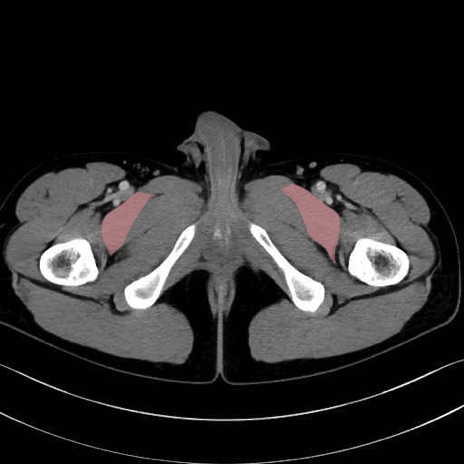

恥骨筋(pubic muscle) のCT画像の解剖

恥骨筋 (Pectineus)